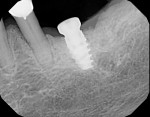

The cast was sectioned 4 mm distal of tooth No. 20. The data from the corresponding cross-sectional cut were transferred to the cast. The ideal buccolingual axis was drawn onto the cast, based on a screw access hole in the central fossa of the future crown. A small hole was drilled at the desired location of the shoulder of the implant. The pin of the Bucco Lingual Positioner (BLP) was placed in the hole, and the central groove of the BLP was lined up with the drawn implant axis. A drop of fast-setting cyano-acrylate glue was applied to lock the BLP in place (Figure 11). The opposing part of the cast was adjusted and the cast was reassembled into the Accu-trac tray. At this point, the buccolingual axis and the top of the implant were irreversibly set, and the mesiodistal could be determined without the risk of making inadvertent changes in the buccolingual plane. The correction slot in the crossbar of the wing assembly fits snugly over the top of the BLP, allowing mesiodistal rotation and mesiodistal translation (Figure 12). Once the correct mesiodistal position was selected, the wings were irreversibly connected to the vacuformed carrier by means of ortho-acrylic (Orthoresin, DENTSPLY International, www.dentsply.com); then the cross-sectional bar was removed, allowing placement of a rotation block. The surgical guide was placed in the mouth and a periapical radiograph was exposed (Figure 13). Note that if the buccal and lingual wings overlap and appear to be one, the radiograph has been taken exactly perpendicular to the ridge, allowing a decision to be made because the image is of acceptable diagnostic quality. In this case, the trajectory was as desired, and the 0º rotation block was selected, as there was no need for rotation adjustments by means of the 3º or 7º rotation blocks (Figure 14). The surgical guide was sterilized in a cold sterilizing solution and the surgery was performed per the manufacturer’s drilling protocol. A 8.5-mm x 4.3-mm implant (NobelActive™ 4.3 x 10 mm, Nobel Biocare, www.nobelbiocare.com) was placed as planned (Figure 15).